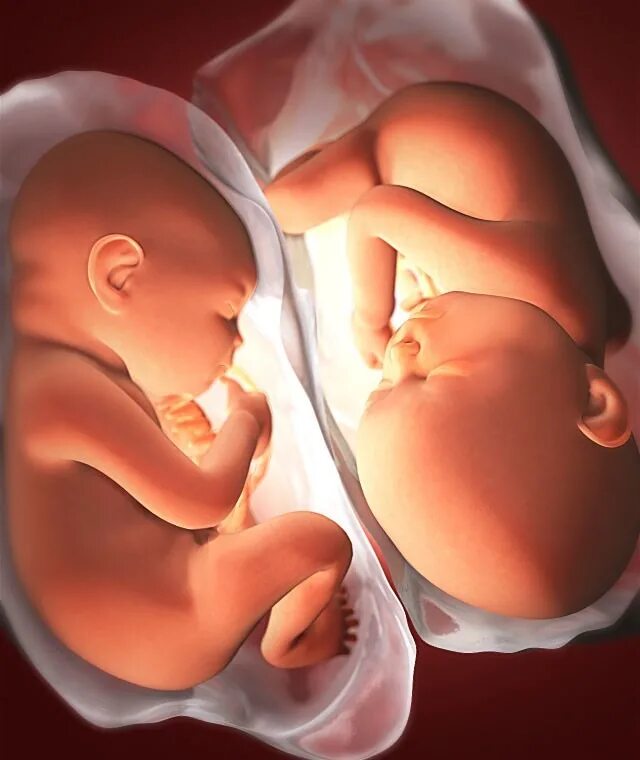

Ребенок в утробе 31 неделя